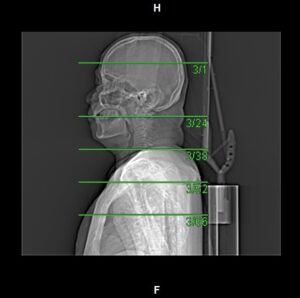

Post Contrast Scan Planning

Monitoring

- Single click on the pre-monitoring image

- Single click again to activate purple circle for triggering

- Drag and drop the circle inside the aortic arch region

- Click TRIGGERING tab

- Set the Hounsfield Unit value to 80

Setting the ROI circle for triggering

Contrast triggering start

Contrast HU reached the trigger value